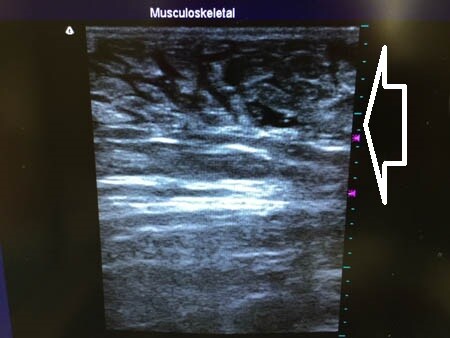

術中の写真を見ていきましょう。 いつものように3Dタッチビューから。

白い矢印部分が皮下脂肪層です。 左太もも正面。